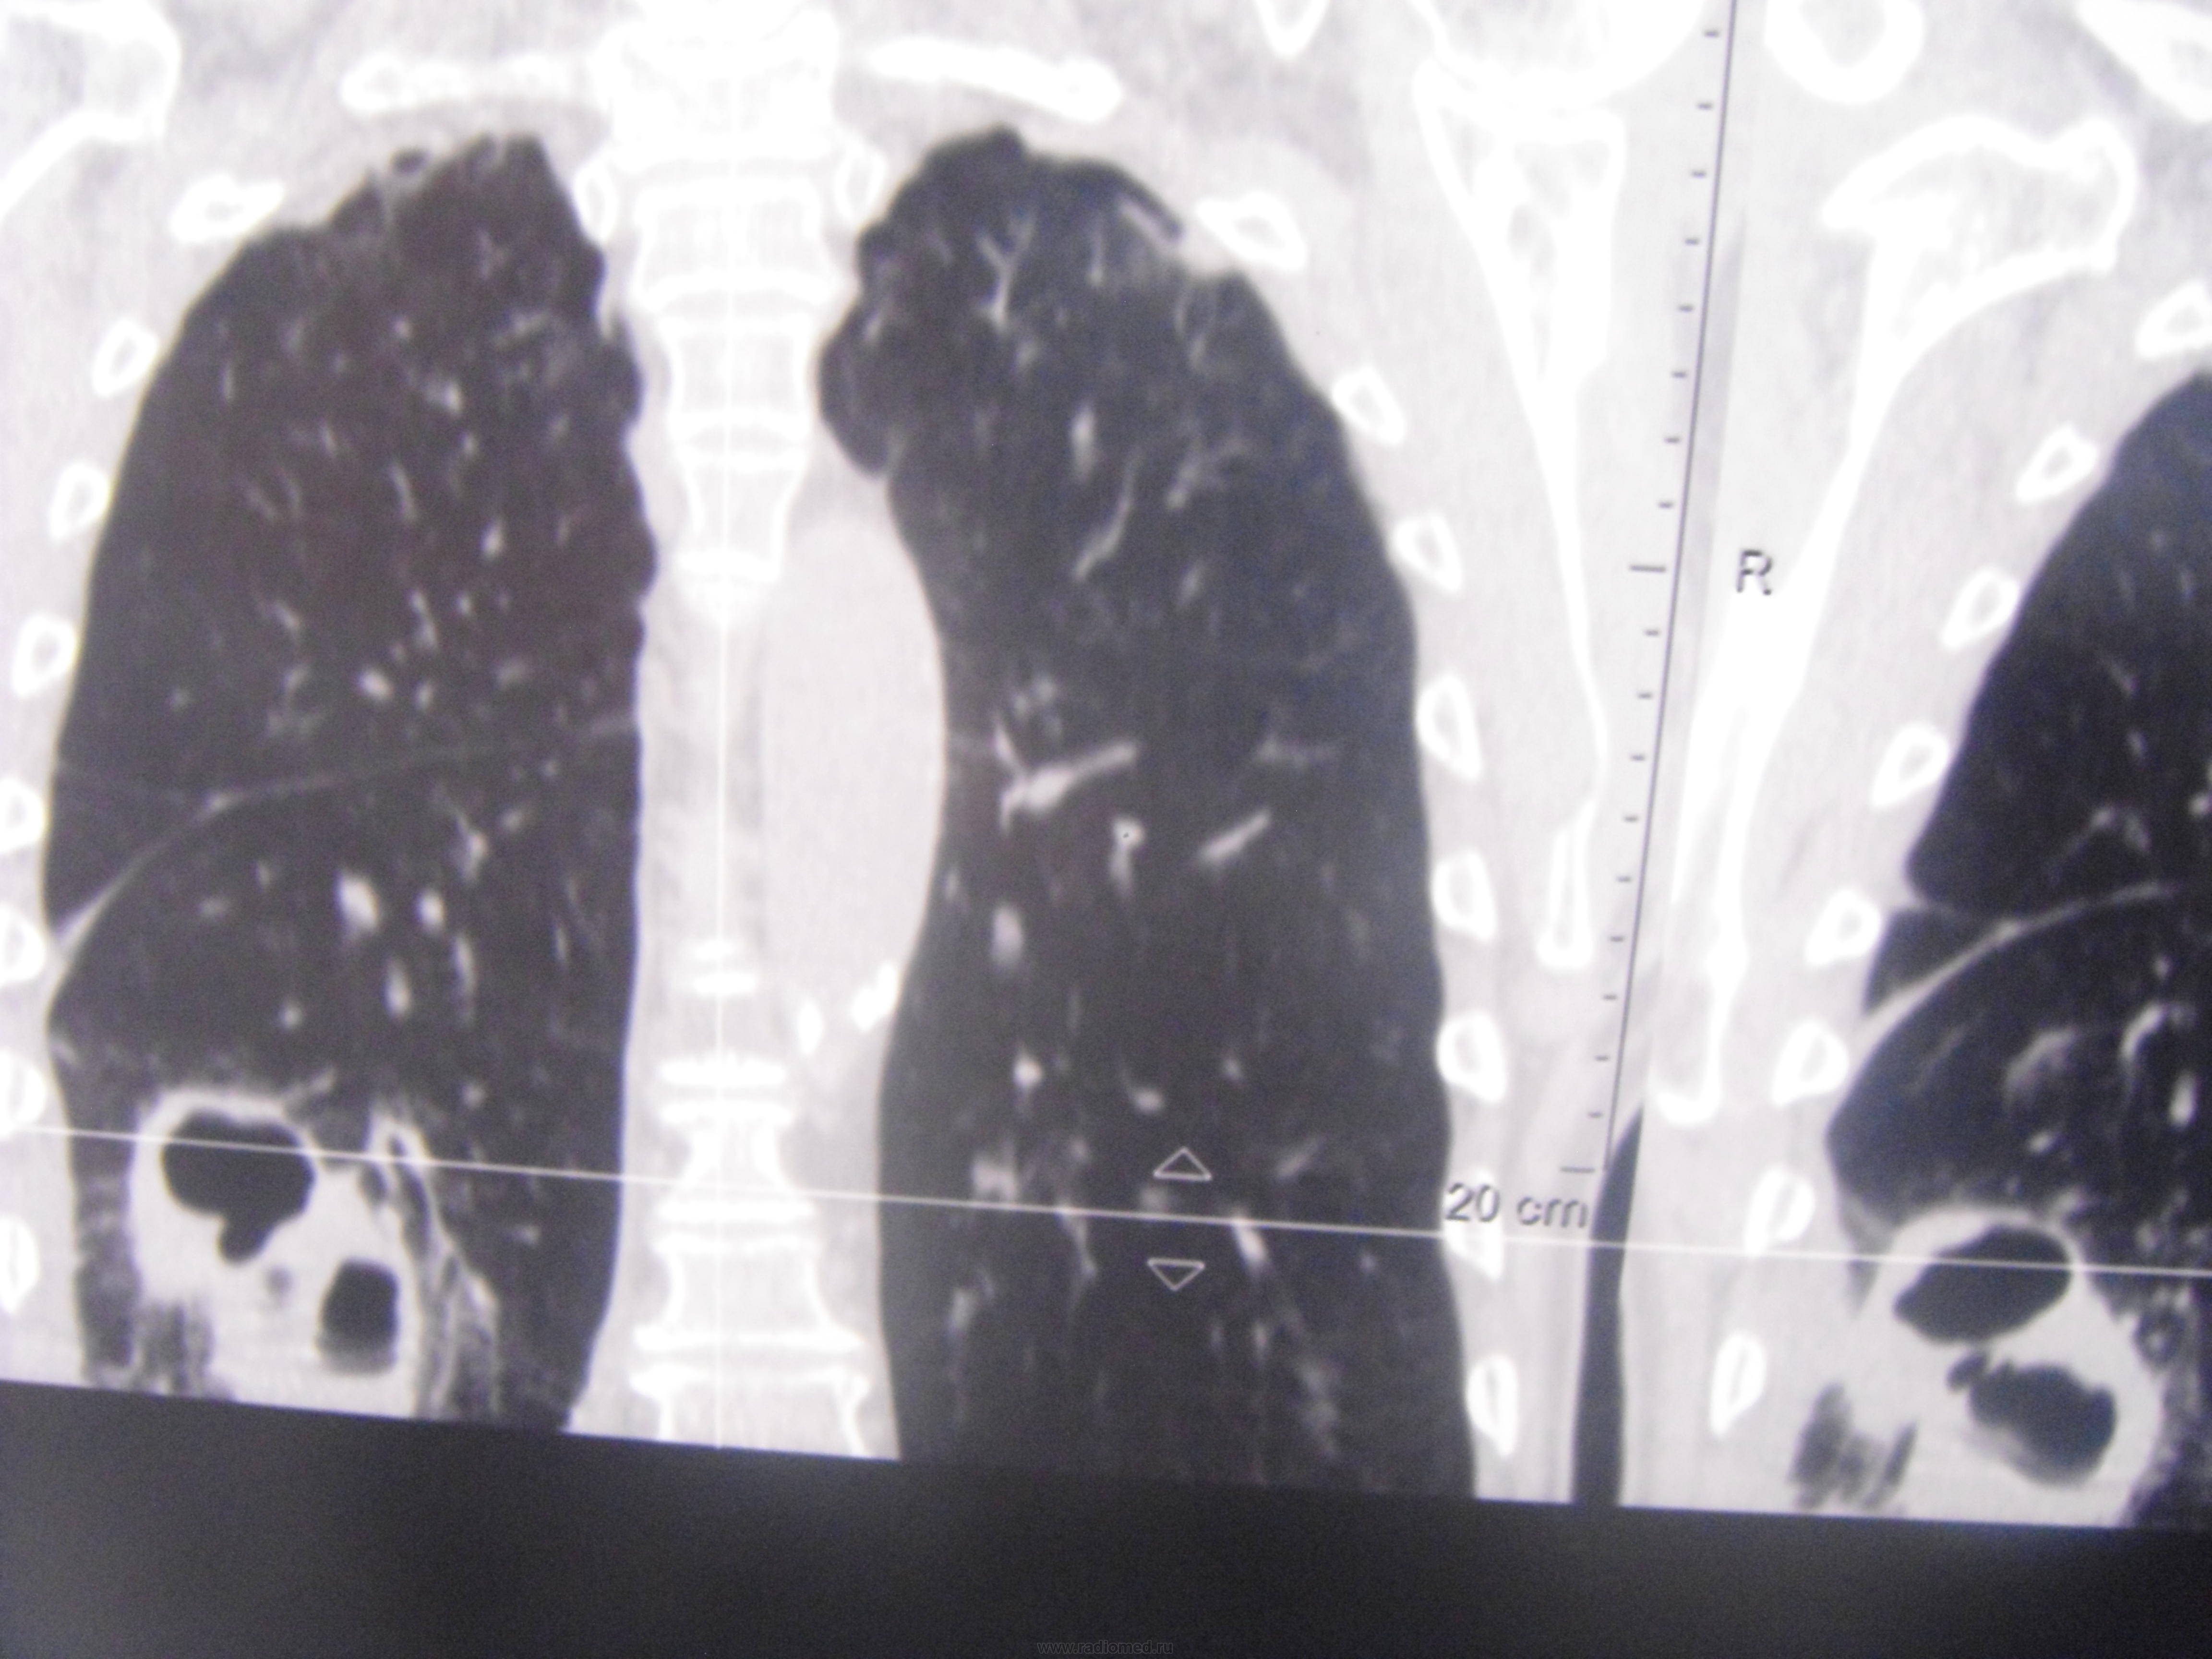

Больной лечился у невролога, провели проф ФГ- выявили деструктивную пневмонию, пролечилили, на Р контроле- ухудшение, клиники абсцесса не было, была боль в гр клетке спереди справа. Из анамнеза- лечился оперативно 6-7 лет назад по поводу рака верхней губы, в ООД не наблюдался последние годы. Данные за туб этиологию сомнительны, как мне кажется, очагов отсева по слоям не вижу,  хотя мож не так смотрю. Ваше мнение коллеги, абсцесс это или нет?

По опыту хочу сказать, что в настоящее время классической клиники абсцесса можете и не увидеть. Очень она изменилась. В данном случае контроль  должен помочь. В связи с тем, что стенки имеют разную толщину и вокруг почти нет изменений, больше склоняюсь к полостной форме рака.